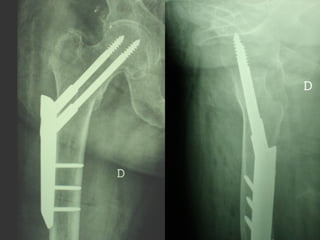

Dal Gennaio 2000 al Dicembre 2005 27 placche LISS di femore

Osso porotico Stabilità con viti autobloccate

INDICAZIONI COMUNI Fratture sovracondiloidee Fratture intercondiliodee Fratture diafisarie distali PARTICOLARI Fratture con grave osteoporosi Fratture periprotesiche

VANTAGGI CHIRURGIA MININVASIVA Mini Open Inserimento della placca sottocutaneo per scivolamento Viti percutanee Preservazione dei tessuti molli Ridotto danno vascolare Rapida ripresa funzionale

F, 68 y

LISS  NCB

NCB

Conclusioni Riduzione  anatomica Minimo trauma chirurgico Corretto equilibrio fra elasticità e stabilità Precoce mobilizzazione